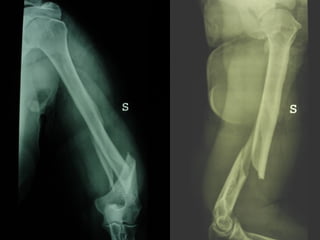

Dal Gennaio 2000 al Febbraio 2006 abbiamo trattato 167 fratture chiuse  con placca percutanea  in 164 pazienti :  27 lesioni diafisarie di gamba, 12 piloni tibiali ,  11 fratture prossimali di tibia, 36 fratture sovracondiloidee di femore, 17 fratture diafisarie di femore, 43 fratture metaepifisarie prossimali di omero, 21 diafisarie d’omero.  156 guarigioni 8 fallimenti

I buoni risultati ottenuti dipendono da 5 punti fondamentali:   una accurata riduzione percutanea della frattura  precise vie di accesso  l’utilizzo della placca che consenta il più lungo braccio di leva possibile il pretensionamento della placca  una sintesi con un ridotto numero di viti

Accurata riduzione percutanea della frattura